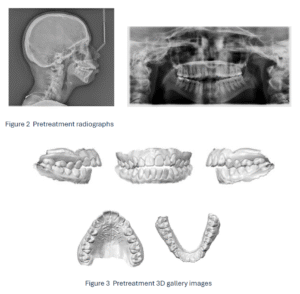

fig 2 and 3